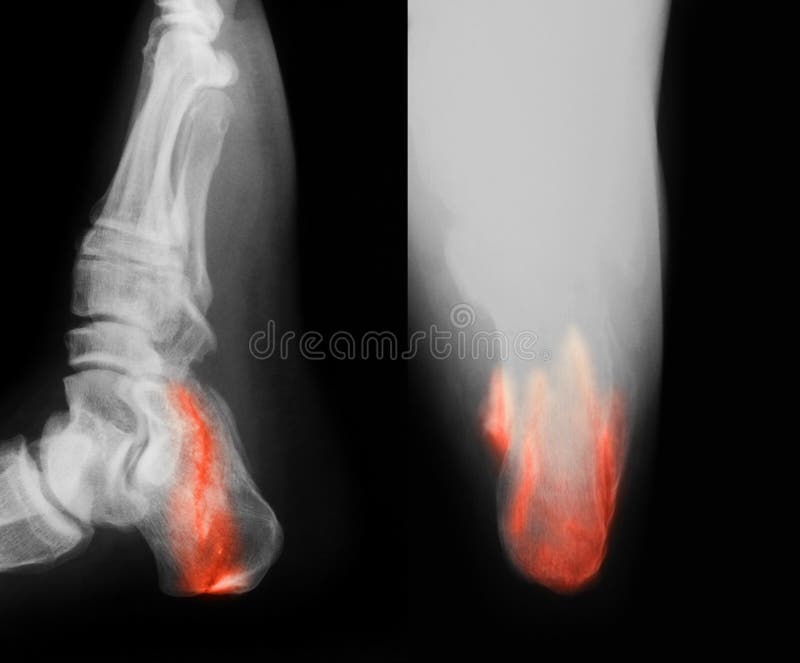

From www.dreamstime.com

Broken Heel Xray Fixed with Screws and Plate, Foot Pain at Doctor Foot Pain Xray [1] may not be sufficient to identify malleolar fractures. Calcaneal apophysitis, also known as sever disease, is the painful inflammation of the apophysis of the calcaneus. Most arthritides are best evaluated with plain radiography. Bony tenderness at the base of the 5th metatarsal. It typically presents in active. If pain is severe enough or if there has been an injury,. Foot Pain Xray.